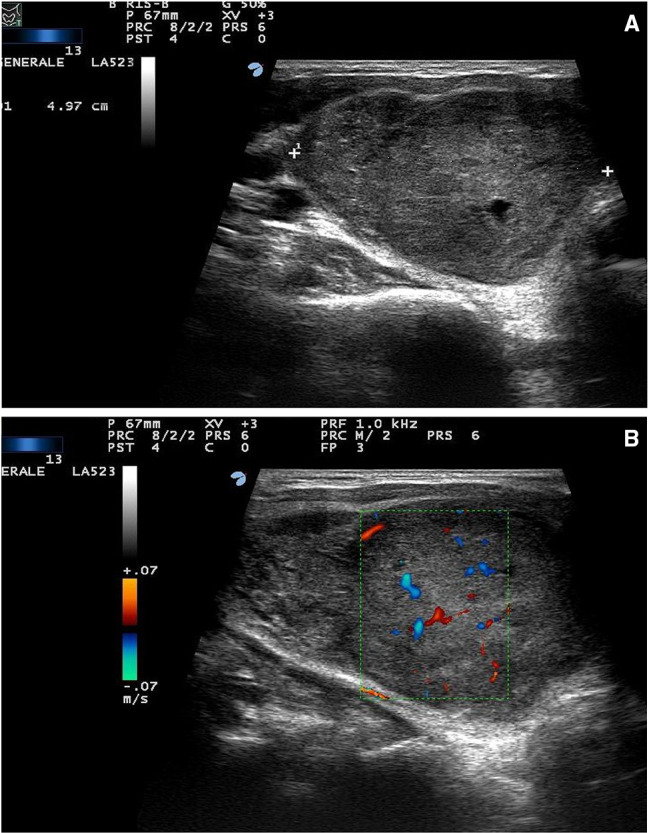

A 40-year-old man was referred to our thyroid outpatient clinic for the progressive growth of an anterior neck mass. US examination revealed a solid, hypoechoic lesion with heterogenous structure and lobulated margins in the right thyroid lobe. It measured 65 × 44 × 40 mm without sonographic evidence of infiltration of the thyroid capsule and surrounding tissues (Fig. 1a). No lymph node pathology was identified by neck US examination, and color-Doppler evaluation showed only scant intranodular vascular signals (Fig. 1b). Due to the worrisome clinical and sonographic findings, the patient underwent US-guided FNA according to previously described techniques [7]. Cytologic smears showed tissue fragments with clusters of small cells demonstrating a high nuclear-to-cytoplasmic ratio, round nuclei, coarse chromatin, inconspicuous nucleoli, and scant cytoplasm (Fig. 2). Cytologic features consistent with PTC were not identified. The cytologic sample was classified as Bethesda V: suspicious for malignancy [8].

Fig. 1.

Ultrasound scan of the right thyroid lobe. a Deeply hypoechoic nodule, 50 × 60 × 35 mm, with heterogeneous structure and slightly lobulated margins; b Color-doppler evaluation demonstrates scant intranodular vascular images. No sonographic evidence of thyroid capsule infiltration